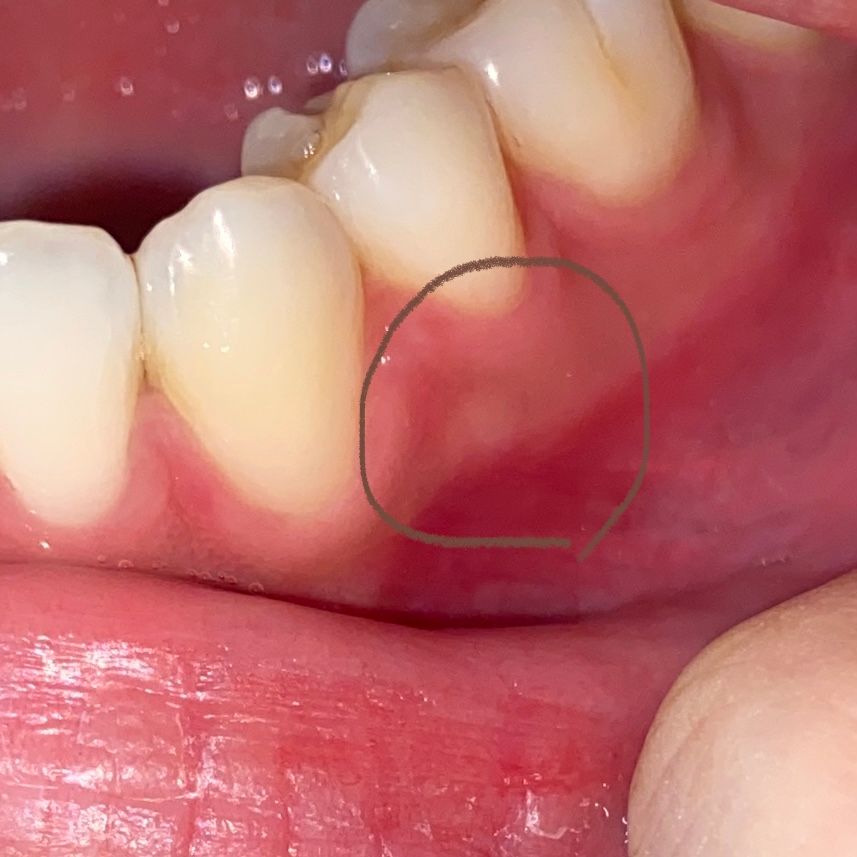

잇몸에 하얀 부분이요, 혹시 잇몸 염증 초기일까요?

사진에 표시된 흰 부분을 눌러보니 딱딱하고 아프진 않습니다.

그렇지만 저게 잇몸 염증이나 고름주머니의 초기 모습일까봐 너무 신경쓰이네요.

• 2번 째 사진

잇몸뼈로 판단되며 혹시 크기가 커지거나 한다면 치과에서 검사를 받아보시면 되겠습니다.

치조골이 나온부위가 딱딱하다면 고름주머니의 가능성은 낮습니다 .

치조골의 뼈가 밖으로 자라 나오는 외골증의 가능성이 있습니다.

외골증은 크게 문제를 일으키지는 않는 경우가 많아요.

고름이 아니시고 잇몸뼈가 튀어나오신거 같습니다. 고름은 여드름 처럼 볼록 튀어 나와서 말랑하지만 사진상에서 고름처럼 보이지 않고 잇몸뼈 같습니다.